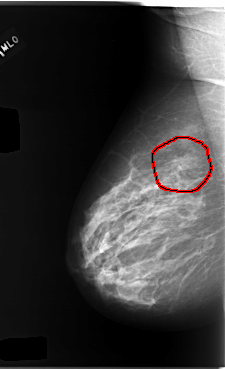

C_0095_1.RIGHT_MLO

FILE: C_0095_1.RIGHT_MLO.OVERLAY

TOTAL_ABNORMALITIES 1

ABNORMALITY 1

LESION_TYPE MASS SHAPE IRREGULAR MARGINS SPICULATED

ASSESSMENT 4

SUBTLETY 4

PATHOLOGY MALIGNANT

TOTAL_OUTLINES 1

BOUNDARY